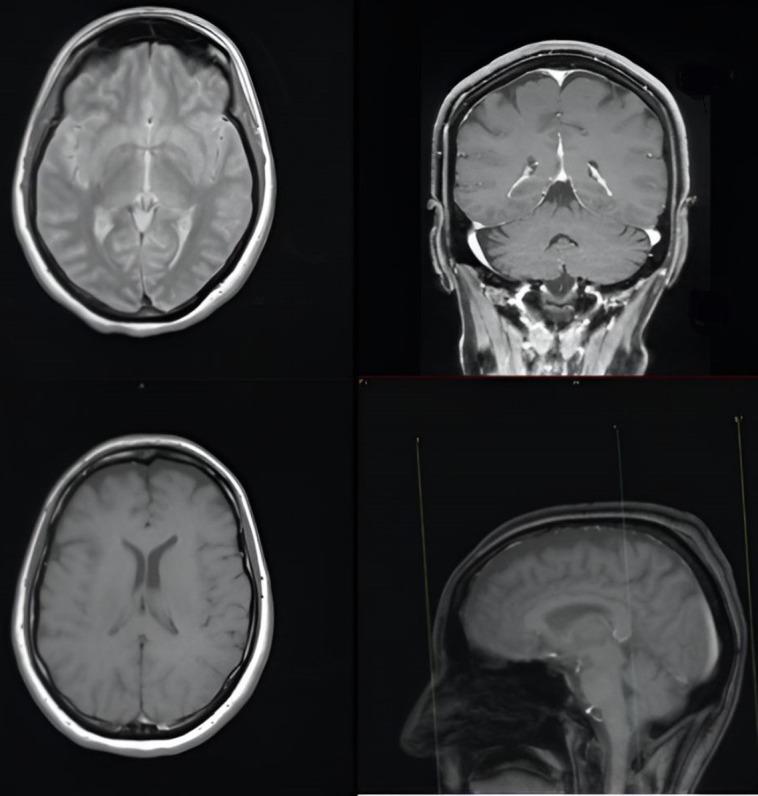

Ocular flutter is an uncommon ophthalmic finding that may indicate paraneoplastic phenomena, and it is clinically characterized by intermittent bursts of conjugate, horizontal saccades without an intersaccadic interval. Ocular flutter must be differentiated from opsoclonus, which, although also characteristic of certain paraneoplastic syndromes, is instead defined by multidirectional saccades on both the horizontal and vertical planes. This report describes a very rare presentation of anti-Ri syndrome in a patient with an undiagnosed breast cancer, presenting with ocular flutter, dizziness, blurred vision, photophobia, and vomiting. Comprehensive evaluations, including contrast-enhanced brain Magnetic Resonance Imaging (MRI), brain Computed Tomography (CT) scan, ophthalmological assessment, viral serology, complete blood count and thyroid, renal coagulation, hepatic function assessments, vitamin D and B12 levels, were all normal. Upon excluding other potential etiologies for the neurological symptoms, a paraneoplastic origin was considered. Serological tests confirmed the presence of anti-Ri onconeural antibodies, and a whole-body CT scan identified nodules in the right breast. Despite surgical excision of the primary tumor and subsequent medical therapy, there was no improvement in the neurological symptoms. Follow-up evaluations at 2 months, 6 months, 1 year and 2 years revealed persistent vestibular and neurological symptoms, with serum tests remaining positive for anti-Ri antibodies and no clinical or radiological evidence of neoplastic recurrence.

眼球扑动是一种罕见的眼科表现,可能提示副肿瘤现象,其临床特征为共轭性水平扫视的间歇性发作,且无扫视间隔。眼球扑动必须与眼阵挛相鉴别,眼阵挛虽然也是某些副肿瘤综合征的特征,但它是由水平和垂直平面上的多向扫视所定义。本报告描述了一名未确诊乳腺癌患者出现的非常罕见的抗Ri综合征表现,患者伴有眼球扑动、头晕、视力模糊、畏光和呕吐。包括增强脑磁共振成像(MRI)、脑计算机断层扫描(CT)、眼科评估、病毒血清学、全血细胞计数以及甲状腺、肾脏凝血、肝功能评估、维生素D和B12水平在内的全面评估均正常。在排除神经系统症状的其他潜在病因后,考虑为副肿瘤起源。血清学检测证实存在抗Ri肿瘤神经抗体,全身CT扫描发现右乳有结节。尽管对原发肿瘤进行了手术切除并随后进行了药物治疗,但神经系统症状并无改善。在2个月、6个月、1年和2年时的随访评估显示,前庭和神经系统症状持续存在,血清检测抗Ri抗体仍为阳性,且无肿瘤复发的临床或影像学证据。